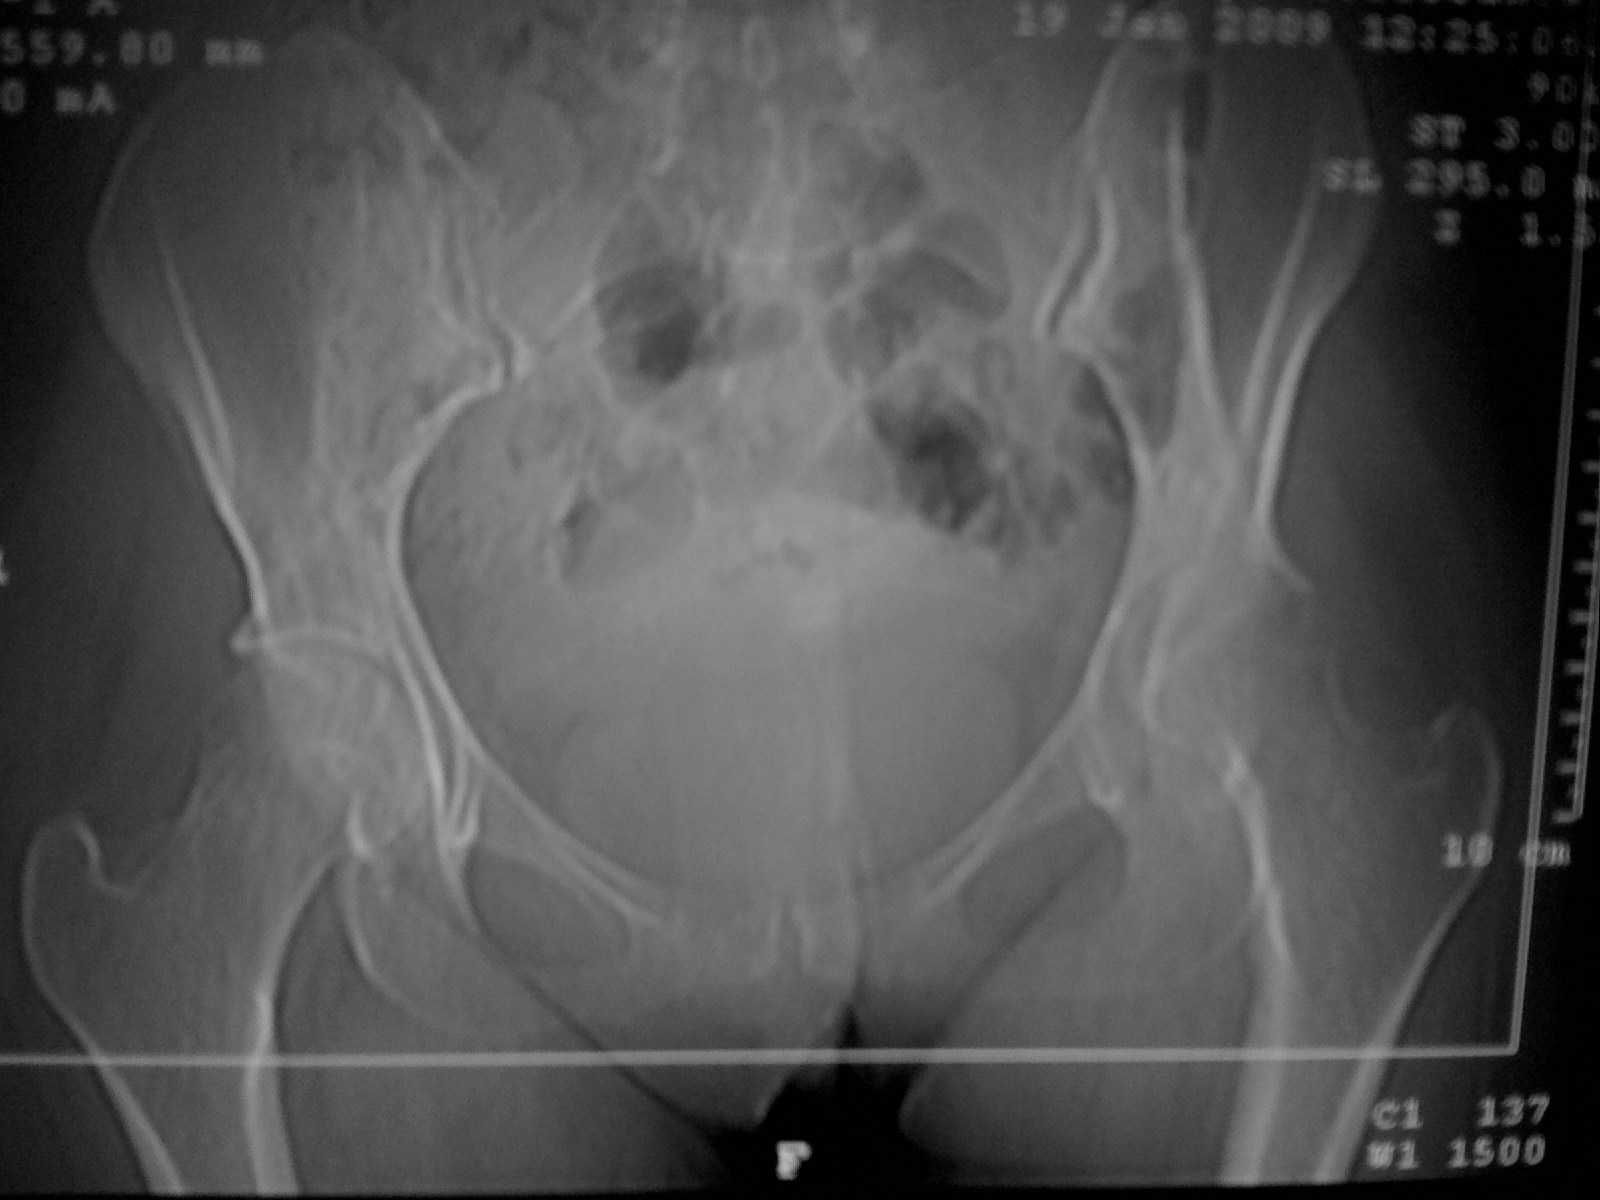

Коллеги! Пациентка 27 лет. Впервые обратилась 6 мес.назад после родов расхождение лонного сочленения, проведена консервативно.

Через 3 мес.повторное обращение по поводу болей в т\б суставе.Ходит с костылями, отведение, приведение в суставе в пределах 10*.Укорочение н\конечности на 3,0см.Непонятен механизм развития данной ситуации и какой метод лечения выбрать. Если протез то какой?

Укорочения по снимку не видно, скорее всего, это из-за приводящей контрактуры. Такое быстрое разрушение сустава может быть при коксите. Нет указаний на инфекцию? Что сейчас - СОЭ, лейкоцитоз, CRP?

Иногда в обзораз среди причин АНГБК у взрослых указывают беременность. Если инфекция исключена, то такая скоротечность для АНГБК подходит. Снимки очень не четкие, как будто делались на бегу. Можете представить снимки в динамике? Что написано в заключении РКТ?

суставы диспластичные, но, учитывая тенденцию к протрузии, лучше исключить ревматоидные проблемы. Если их нет, то скорее всего диспл коксартроз. Протез б/ц, лучше керамику с большой головой.

Дисплазия суставов вряд ли имеет значение в случае артрита тазобедренного сустава. Мы наблюдаем случаи реактивного неспецифического артрита крупных суставов у пациентов с высокой физической готовностью. В ряде случаев обнаружить следы инфекции в суставах (ПЦР) иммуный ответ (Ig крови) не удается с первого раза. Если естиь возможность, то необходимо продолжать мониторинг. Данные по Германии 2005 - 5% всех заболеваний тазобедренного сустава - реактивные артриты (хламидийные, микоплазменные, уреаплазменные, герпетические, и т. п.).

Пациентка наблюдается в течении 6 месяцев. Трижды отрицательные результаты на все инфекции (хламидии и т.д). Интересует вопрос о установки чашки - что за чашка, и следует ли укреплять вертлужную впадину и как?

я бы, вероятно, предпочел кольцо Muller с пластикой чипсами из головки (bone stock и т.д.)